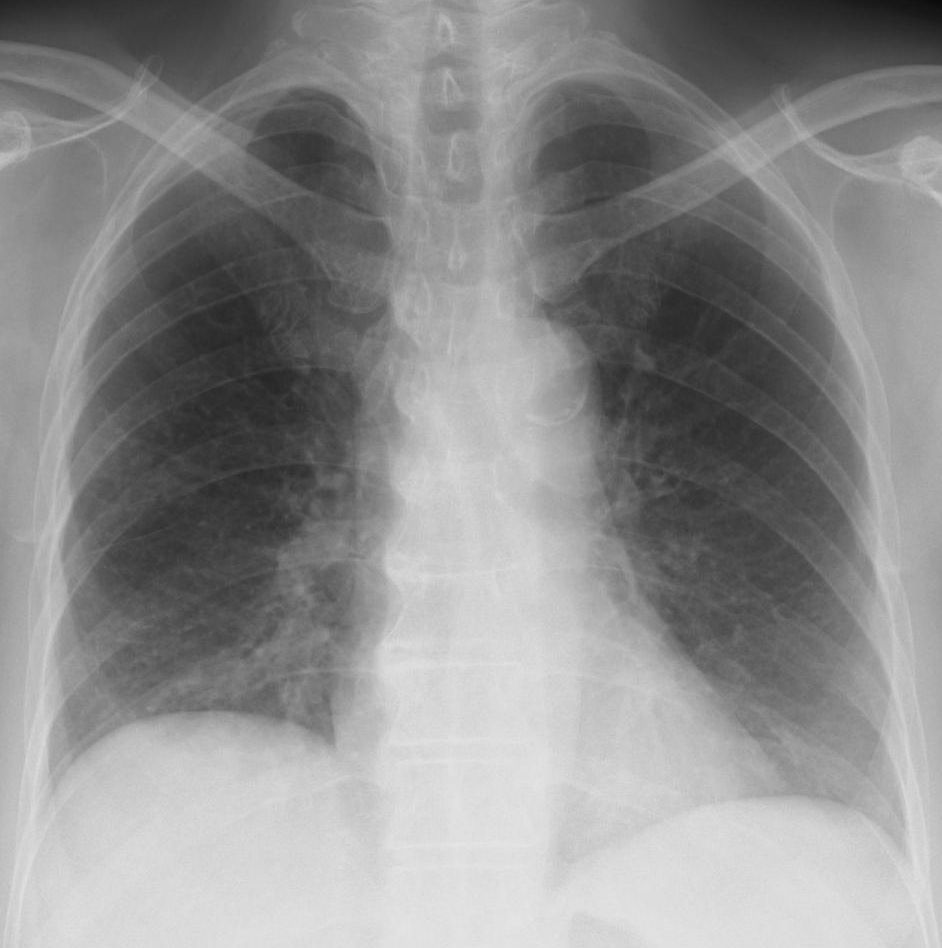

[注意] 心陰影にみえる肺門陰影(右)、シルエットサイン陰性に気づけば肺炎像と理解できる。また、左肺門部陰影は心辺縁が不鮮明(シルエットサイン陽性)で同部にも浸潤影があることが推定できる。 肺門部の浸潤影はいつも慎重に判断する必要がある。下写真の左肺門部の心陰影ははっきりせず(左上挿入写真は治癒時)判断に迷うがシルエット陽性と判断すればS6もしくはS3の肺炎が推定可能になる。下の写真はS6の浸潤影が想定される。 [肺門の陰影]

左は肺門の変化からマイコプラズマ肺炎と診断、オゼックス投与にて解熱しないため3日後に確認したところ浸潤影が拡大していた。 [心陰影の把握]